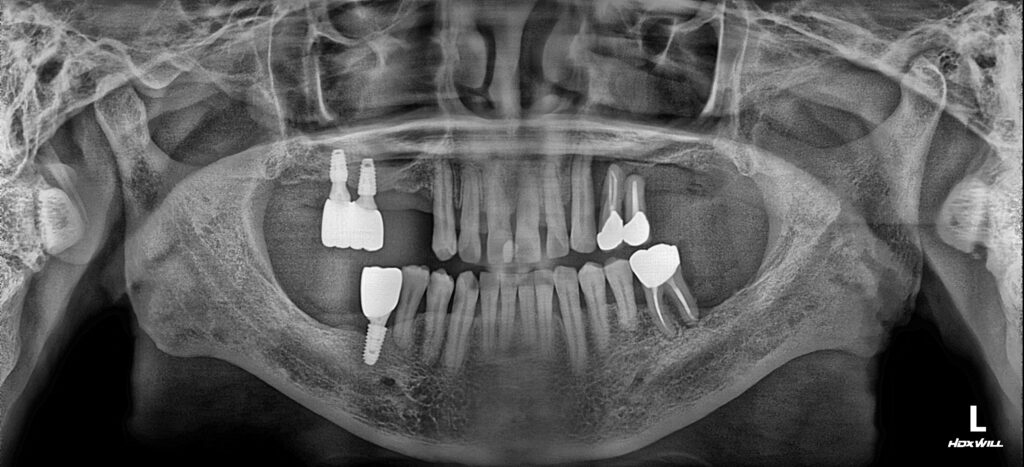

24.10.29

처음 내원하셨을 당시의 모습입니다.

좌측(사진 우측) 끝에 있는 치아들을 보시면 치조골에서 거의 나올 정도로 좋지 않은 상태였기 때문에 발치는 불가피하였습니다. 또한, 좌측 어금니를 거의다 상실하여 갯수도 부족하고, 우측 위 어금니와 아래 마지막 어금니도 상실한 상태로 임플란트로 겨우 식사를 하셨으리라 생각됩니다.